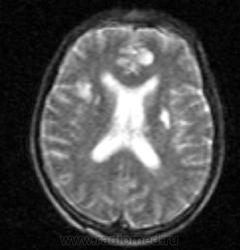

Но кажется в задних рогах кровь.

как интерпретировать очаг в лобной доле слева? и что за кистозно-глиозные изменения в подкорковых яжрах с обеих сторон?

Ну явно не лоб причина его комы. Где "кистозно-глиозная" дырочка на коронарах? В подкорковых - сформированные псевдокисты, кажется есть очаги дистрофических дел, но я как в очках не с тем диоптрием.

Вся надежда-то на флаир - а он весь сияет. Не описуемо. Пусть еще раз привозят на дообследование. Что-нибудь еще предпринималось великими о клиницистами в поисках этиологии комы-неясной-этиологии?

Миндалики ниже линии, и отёк мозга присутствует. Решили, что свежи очаги в ГМ вероятнее травматического генеза.

Отек (?) от токсического поражения или травматического генеза?